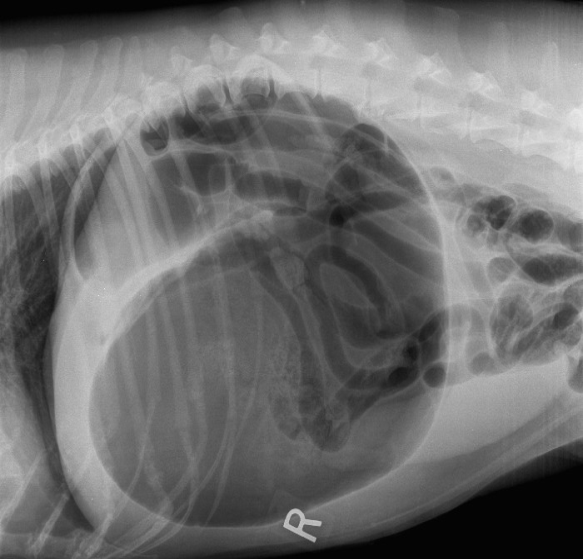

On constate en premier lieu que nous n’avons pas l’image radiographique classique où le pylore se situe craniodorsalement et où il y a une compartimentation de l’estomac.

Latérale droite avec les changements classiques vus lors de volvulus gastrique. Cette image est tirée du site de Cool Springs Animal Hospital.